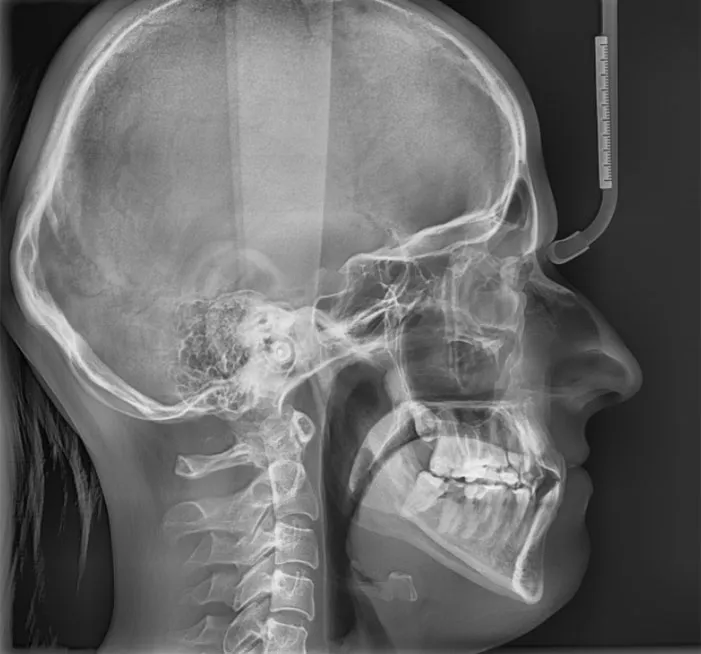

- Pantomogram: To zdjęcie rentgenowskie przedstawiające wszystkie zęby (zarówno stałe, jak i te jeszcze niewyrznięte), kości szczęki i żuchwy, a także stawy skroniowo-żuchwowe. Jest to absolutna podstawa.

- Zdjęcie cefalometryczne boczne: Pozwala na analizę profilu twarzy, ocenę wzrostu kości oraz relacji między szczęką a żuchwą.